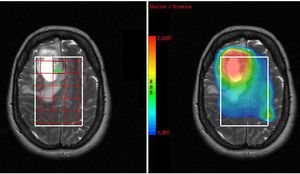

Conventional MR Imaging (MRI) produces anatomical images with thousands of voxels, whose signals reflect the bulk magnetic properties (e.g., T1, T2, susceptibility, flow etc) of the tissues they contain. MR Spectroscopy (MRS) produces spectra in a small number of (larger) voxels reflecting small metabolite molecules differentiated by their chemical shifts (δ). MRS allows tissue to be interrogated for the presence and concentration of various metabolites. Grossman and Yousem said "If you need this to help you, go back to page 1; everything except Canavan has low NAA, high Choline". This is perhaps a little harsh, however it is fair to say that MRS often does not add a great deal to an overall MR study but does increase specificity, and may help in improving our ability to predict histological grade.